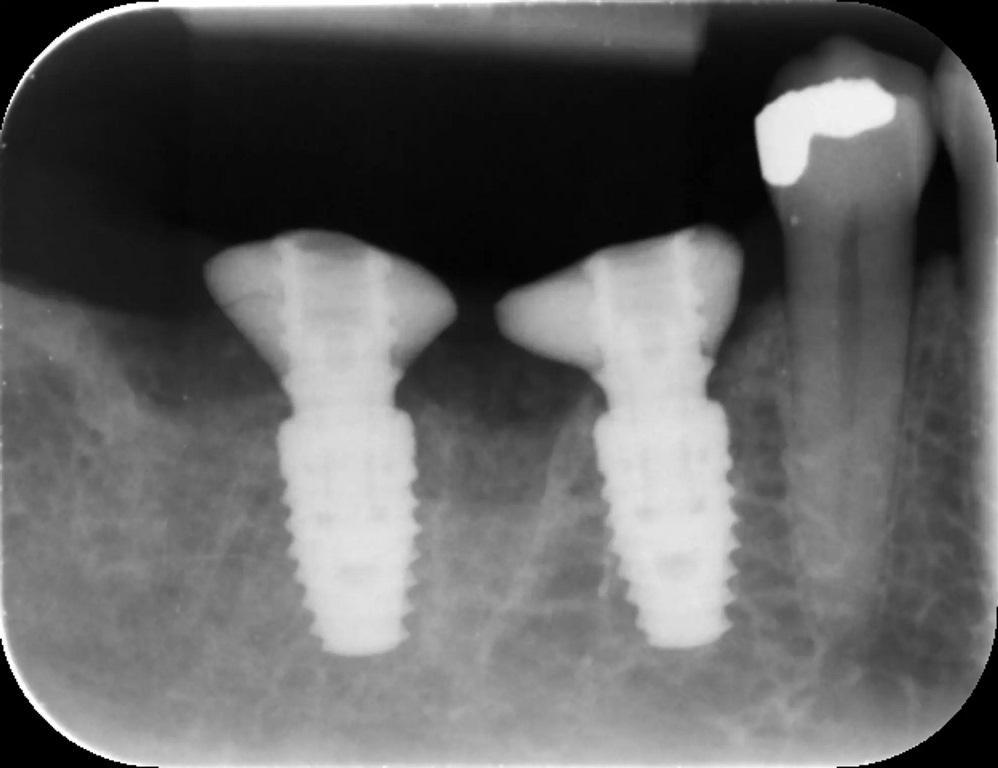

Затем с помощью хирургической направляющей без рукавов и набора CONELOG были установлены имплантаты (5×9 мм CONELOG PROGRESSIVE-LINE, BioHorizons Camlog) (фото 9-10).

Фото 9: Имплантаты устанавливаются с использованием хирургической направляющей для обеспечения точности.

Фото 10: Имплантаты на месте, состояние после графтинга.

После проверки правильности установки имплантата на место имплантации до уровня кости был уложен аллографт MinerOss Putty (BioHorizons Camlog), чтобы уменьшить скопление трансплантационного материала в мягких тканях.